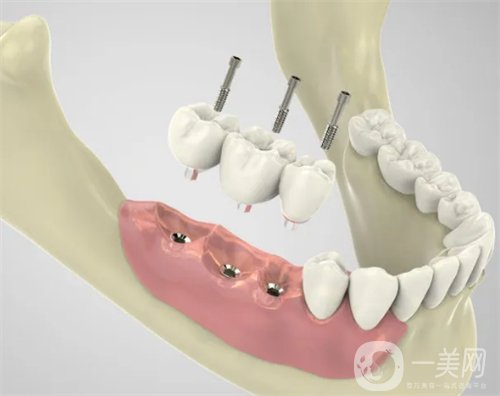

三、天津爱齿口腔种植牙案例

我掉的那颗牙齿是因为我咬东西的时候不小心要掉了一半,后来牙齿松动直接就掉了。估计大家可能还会嘲笑我怎么这么没出息,吃东西都可以把自己的牙齿给割掉,其实我想说的是实在是太寸了,真的没有想到我的牙齿会这么脆弱。有一个牙洞实在是太别扭了,到口腔医院让医生给我看了一下,说是可以做种植牙这个手术来补上之前那个牙洞。医生简单的和我说了一下,种植牙是一个怎么样的手术,以及手术的大概过程和术后修复。

做完种植牙已经四个半月的时间了。现在我的那颗牙齿早就已经种好了。在种好了之后我特别小心的使用着,可牙齿医生还告诉我这颗牙齿是特别坚固的,比我自己长的那些牙齿还要兼顾,让我放心好了,现在的我吃东西一切都恢复了正常。我感觉*近几天都让我长胖了,毕竟每天胡吃海塞的。